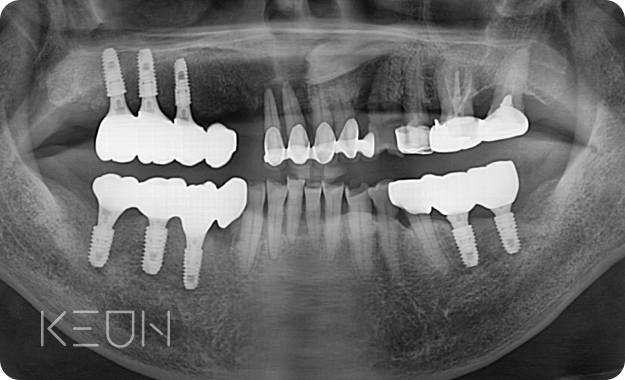

뼈이식 임플란트 전후사진.

- After

*모든 치료전/후 사진은 환자분의 동의하에 촬영 및 게시되었습니다.